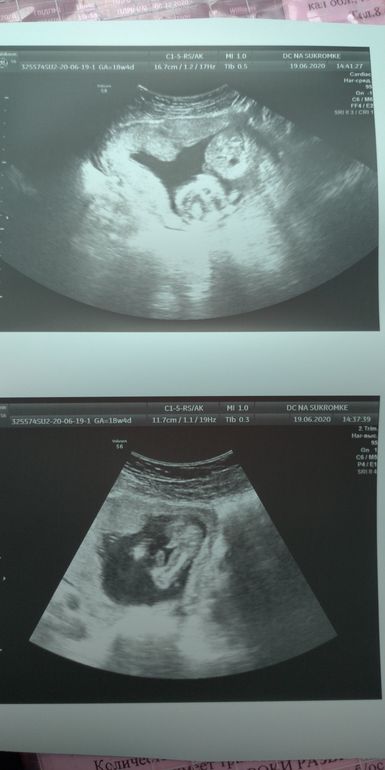

Сегодня прошла второй скрининг)! Вообще не переживала и не нервничала!

Как всегда в нашей ЖК все проходит сухо, без комментариев и только в конце буркнули мне "мальчик, все хорошо!". Ну спасибо хоть на этом!) Я с 15 недель знаю точно, что будет сын у нас...